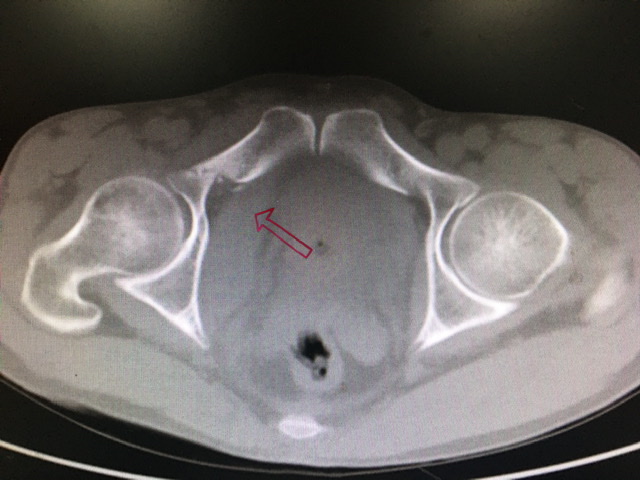

红箭头所指是右耻骨上支骨折,也是后期手术要处理的部位。